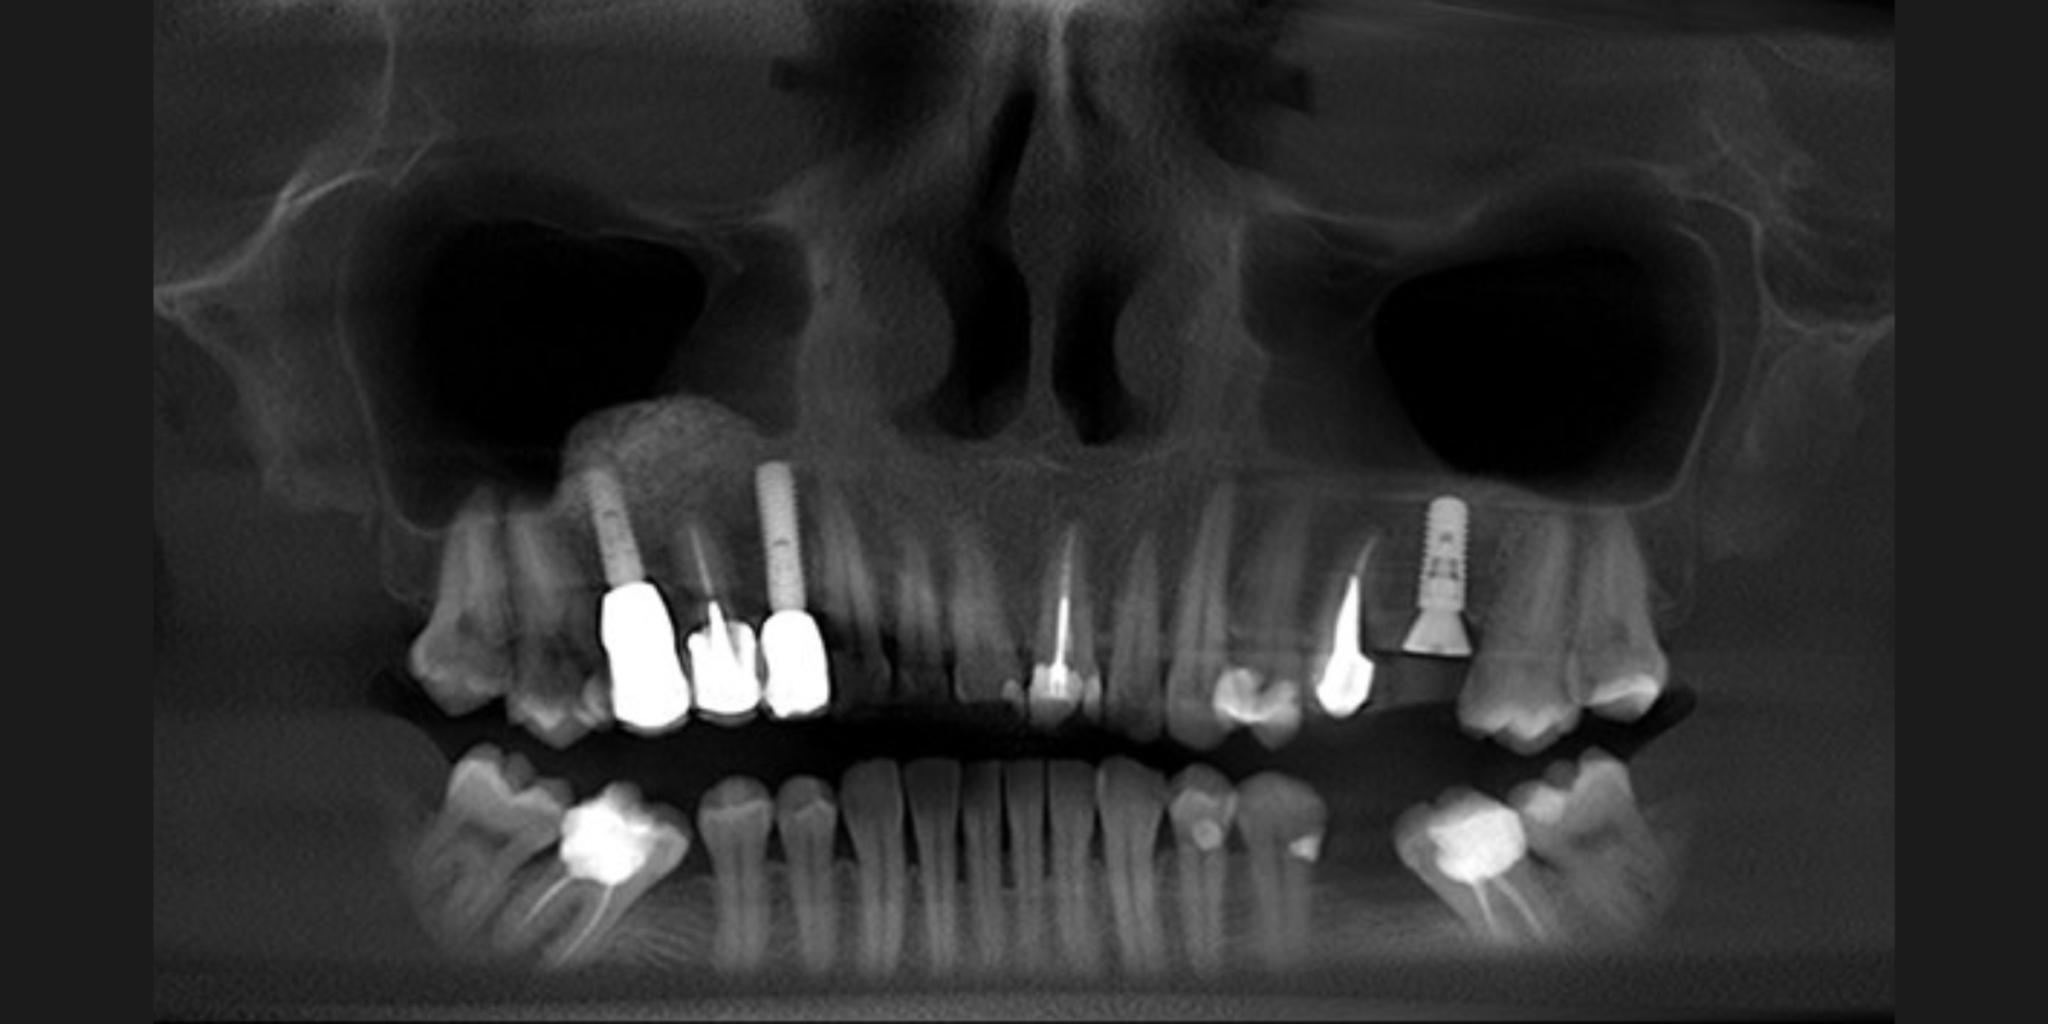

Immediate implant placement allows clinicians to replace a tooth at extraction, reducing treatment time while maintaining bone and soft tissue contours. When guided by the ITI SAC Classification and meticulous planning, it offers predictable, esthetic outcomes — proving that efficiency and precision can go hand in hand.